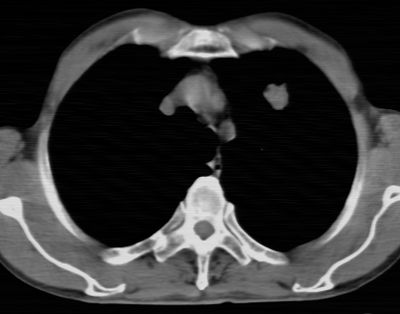

标题: CT24783:m71,既往肺心病史3年,现咳嗽,憋喘。 [打印本页]

标题: CT24783:m71,既往肺心病史3年,现咳嗽,憋喘。

1、左肺上叶spn,毛刺+分叶+血管集束征,考虑周围型肺癌可能性大

2、全小叶性肺气肿。

1)左肺上叶周围型肺癌可能。2)两肺全小叶型肺气肿。

左上周围型肺癌,全小叶型肺气肿。